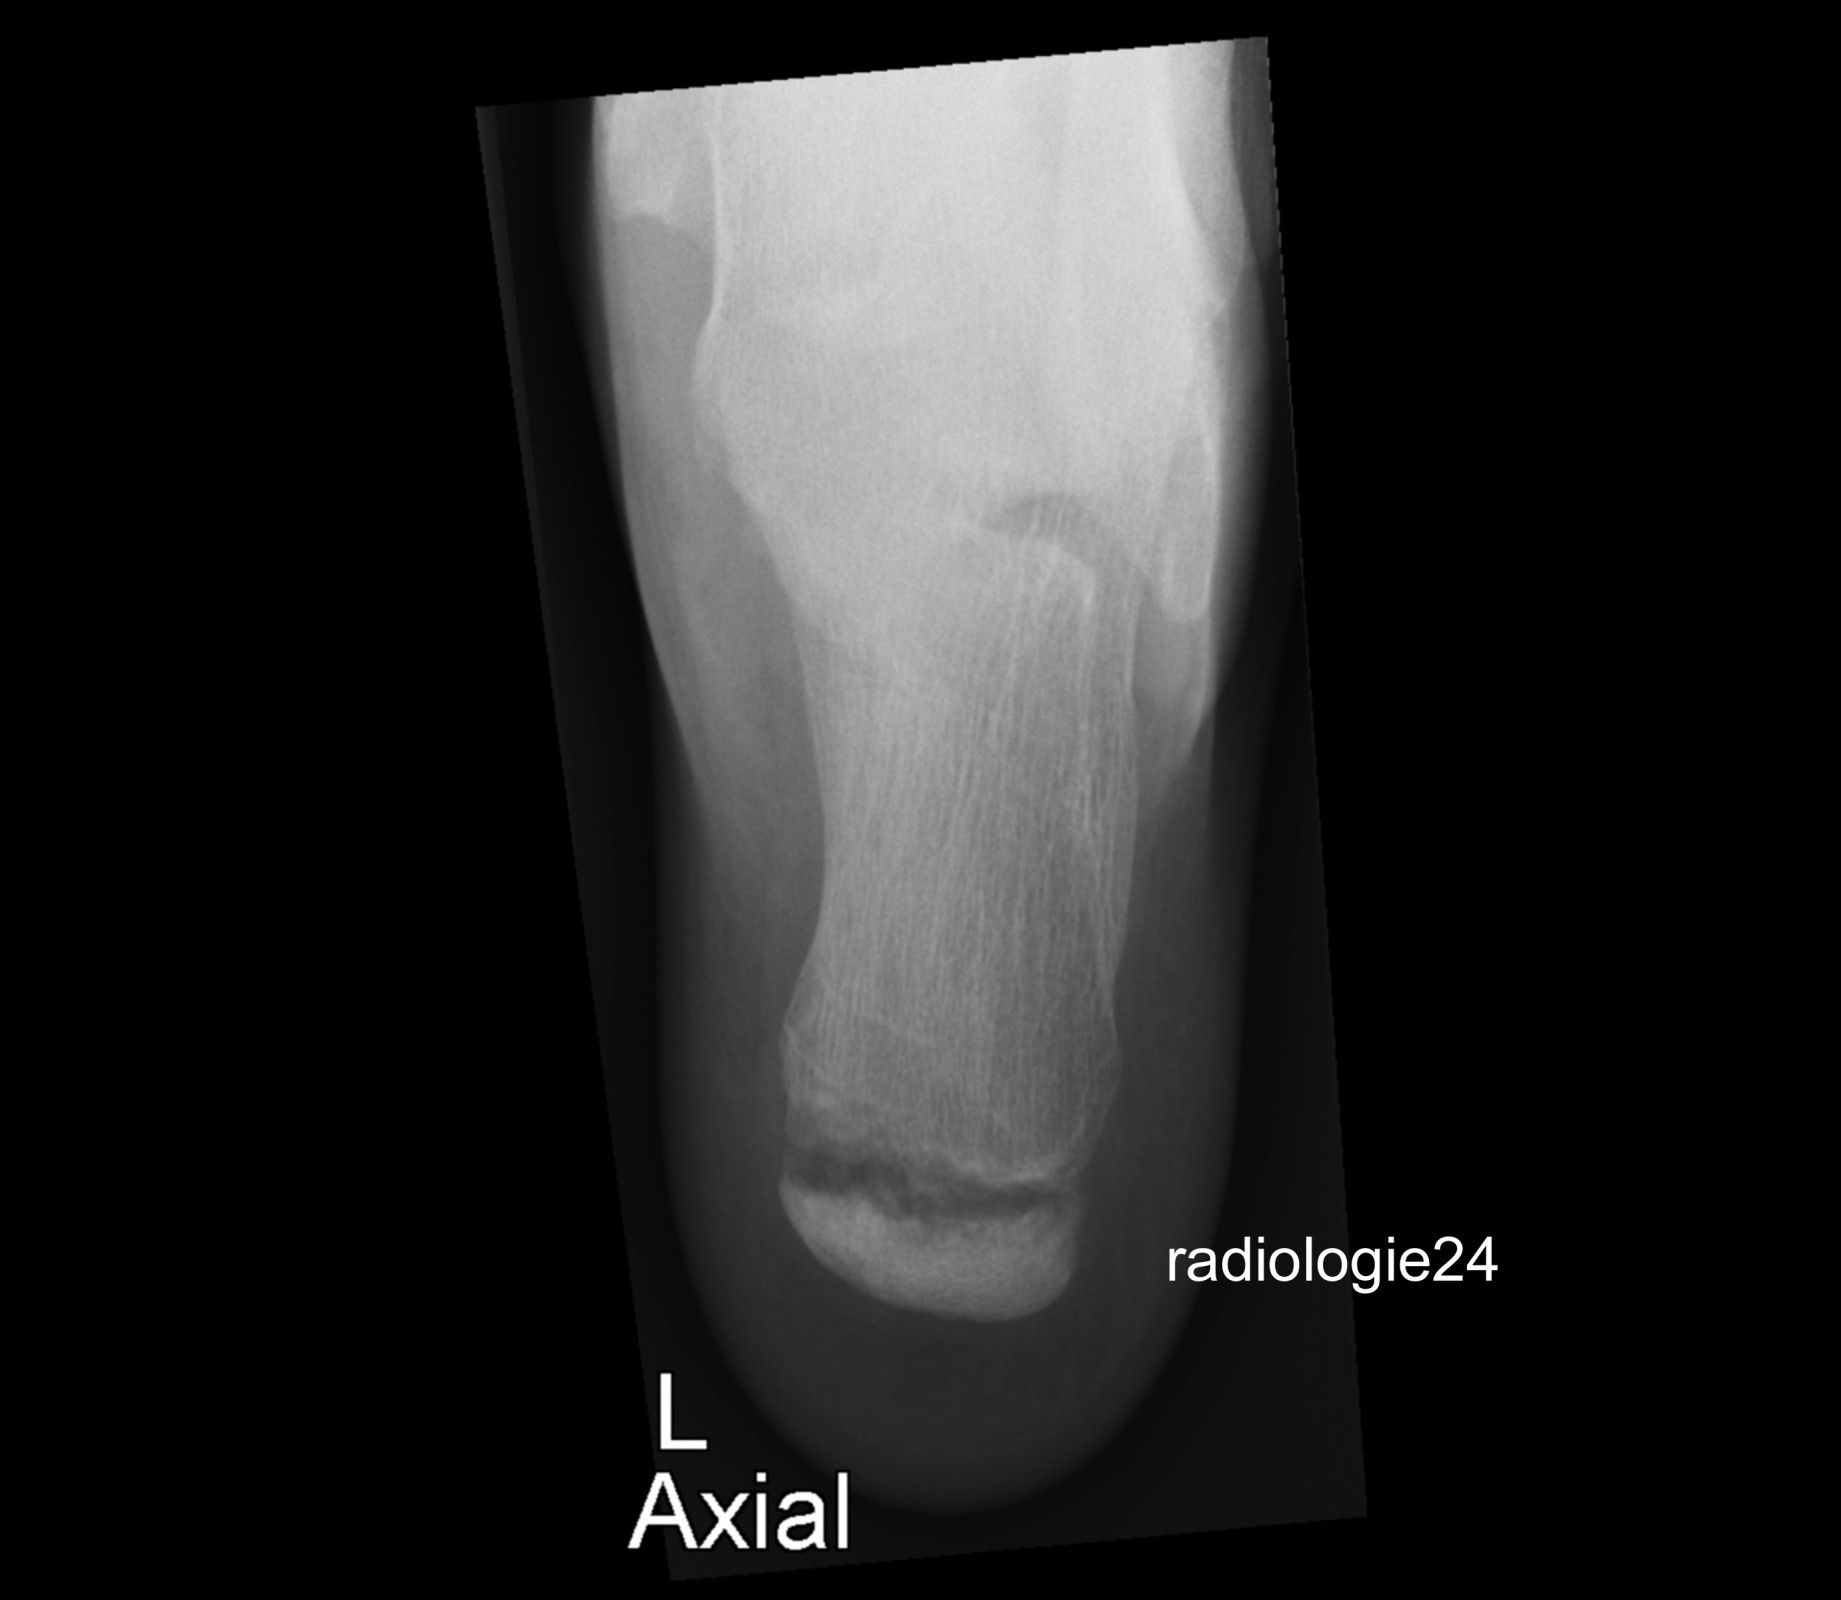

Röntgenfall des Monats April 2018 mit Auflösung

10 jähriger Patient Schmerzen im Bereich des Achillessehnenansatzes nach Fussballspiel. Ihre Diagnose? Weitere Abklärung?

Bild vergrössern

Link zur Auflösung mit ausführlichem Befund:

https://www.radiologie24.ch/radiologie-mediathek/roentgenfall_des_monats